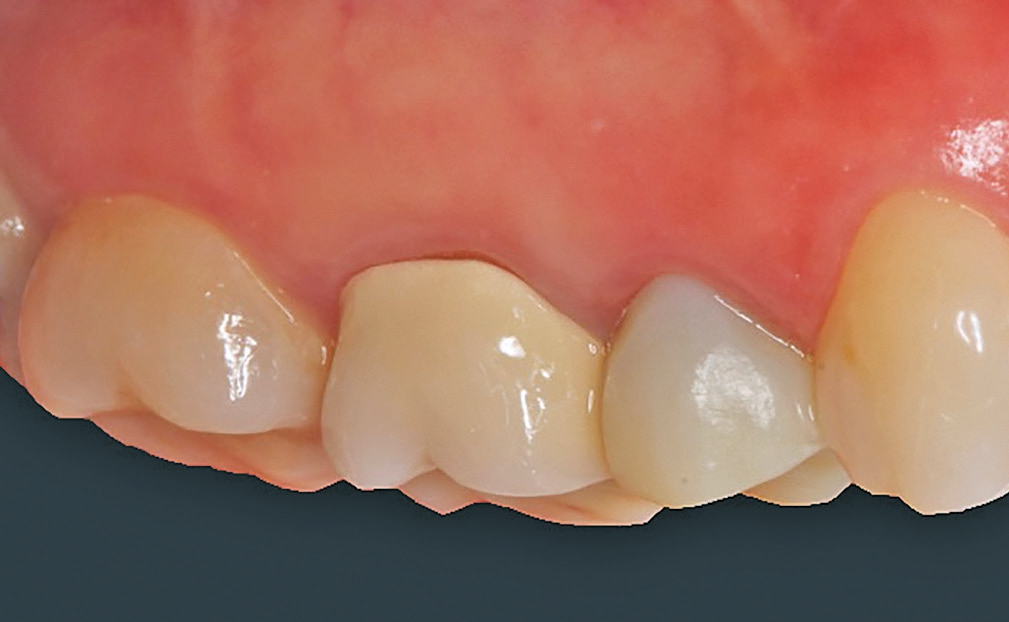

Nach einer komplikationsfreien Einheilzeit von vier Monaten konnte mit der Herstellung des definitiven Zahnersatzes begonnen werden. Hier entschied man sich konsequent für monolithische Kronen aus Lithiumdisilikat, um das Chippingrisiko so gering wie möglich zu halten [12]. Im Zuge der Implantatversorgung wurde nun auch – wie geplant – die metallkeramische Krone an 16 geschlitzt, entfernt und der Stumpf nachpräpariert. Implantatkopf und Zahnstumpf wurden daraufhin zusammen mit A-Silikon analog abgeformt. Für die geschlossene Abformung wurde die Abformkappe (impression.transfer) auf dem Implantatkopf positioniert. Ein deutliches Einrasten signalisierte den lagestabilen Sitz. Für die Modellherstellung rastete das Implantatanalog (lab. replica) ebenso in die integrierte Abformkappe ein. Nach der Herstellung des Meistermodells konnten die beiden Kronen im digitalen Workflow CAD/ CAM-gestützt gefertigt werden. Nach Ausarbeitung, Bemalung und Glasur waren die beiden Kronen für die definitive Zementierung bereit. Die klinische Einprobe der Restaurationen verlief erfolgreich, sodass die Kronen nacheinander mit selbstadhäsivem Befestigungskomposit eingegliedert werden konnten.